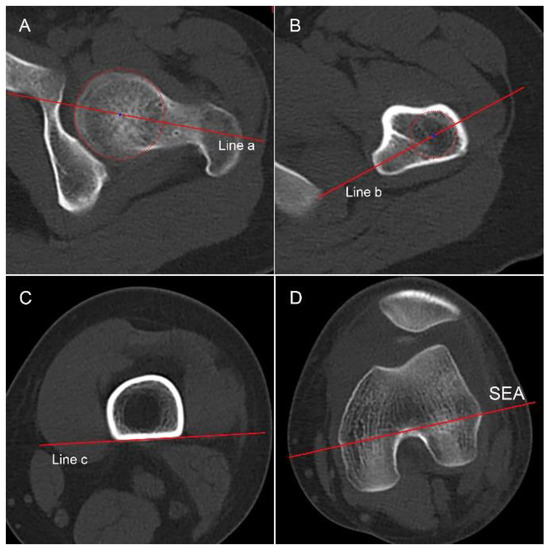

2.3.3. Femoral Anteversion

2.3.4. Knee Joint Rotation and Tibial Torsion